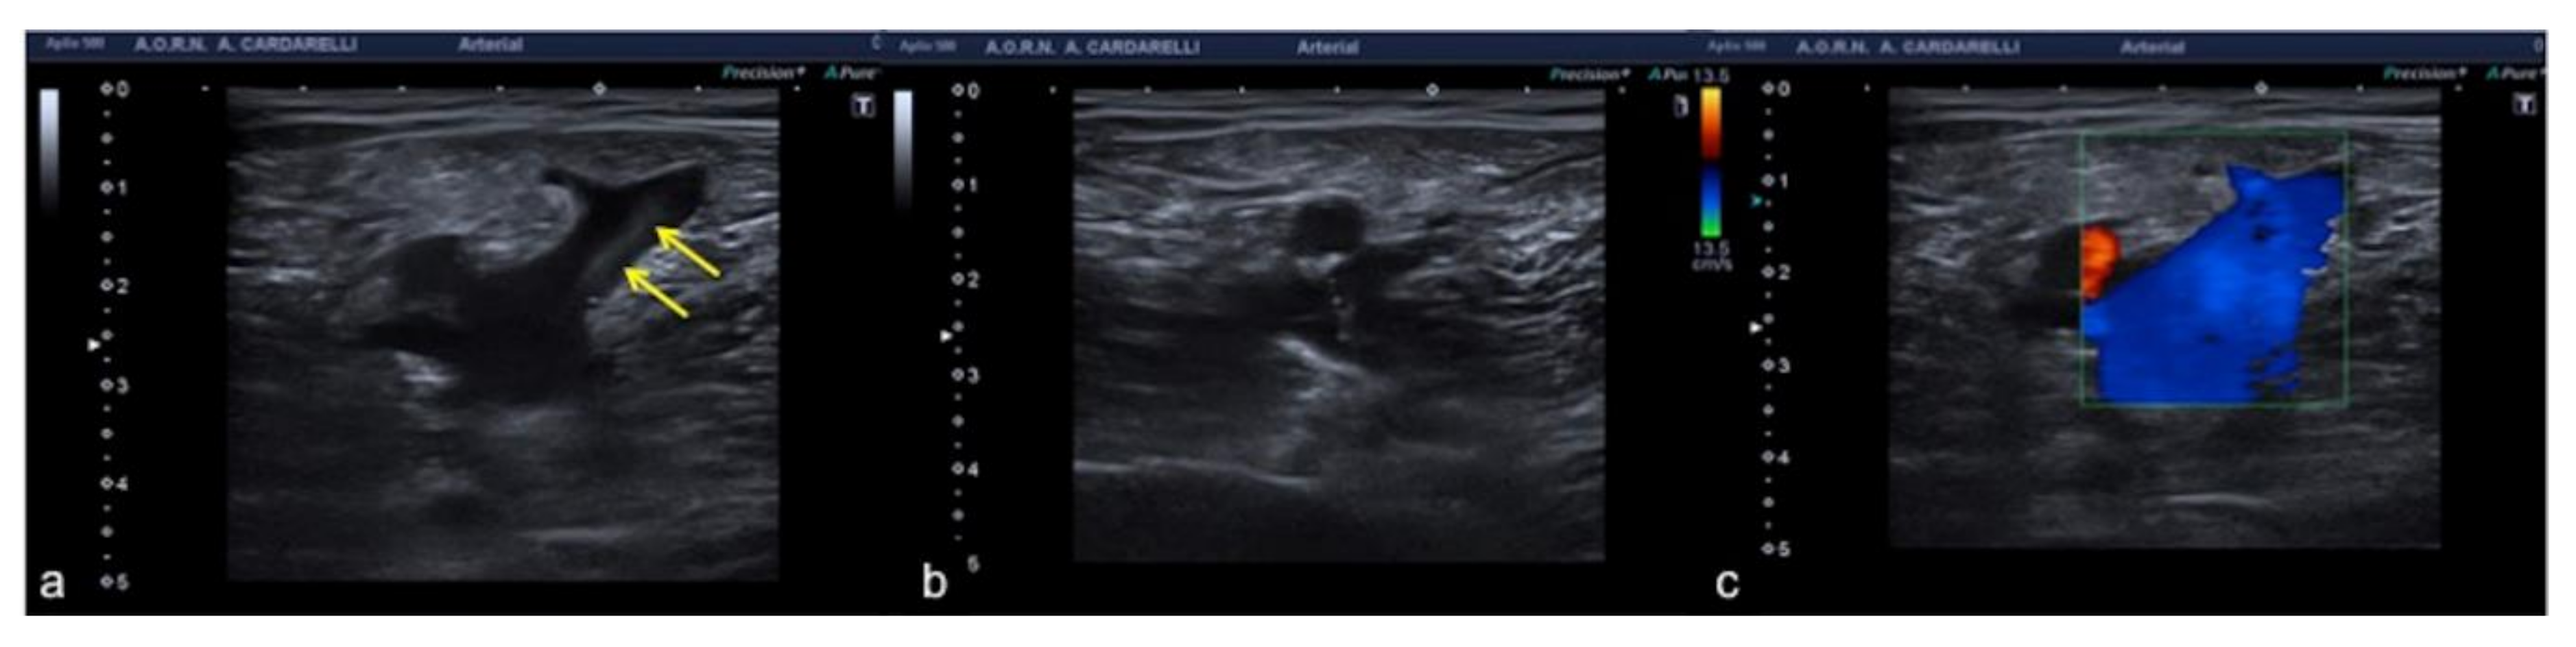

3.1.7. Anisotropy